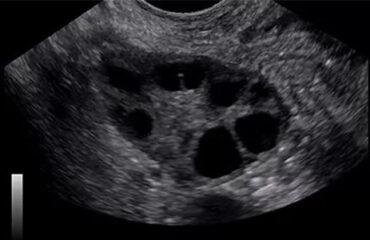

- Κύστεις ωοθηκών